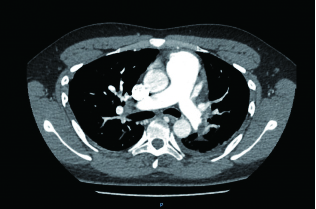

2 积极寻找补救性溶栓的治疗时机并非遥不可及例3 36岁,女性。主诉“活动后气短5 d、加重伴咯血1 d”。既往因月经不调,应用激素替代治疗20 d;否认手术、外伤及制动史。入院查体:神志清楚,体温36.8℃,血压110/75 mmHg,脉率118次/min,呼吸23次/min,脉氧饱和度90%(安静,空气氧),轻度乏氧征。双肺呼吸音清。心率118次/min,未闻及干、湿性啰音,心律齐,P2 > A2,心界无扩大,无杂音,腹软,无压痛,肠鸣音正常,双下肢无浮肿。神经系统查体未见异常。血气分析(空气氧)提示pH 7.415,PaCO2 38.3 mmHg,PaO2 89.90 mmHg,SaO2 89.90%;D-Dimer 1 684 ng/mL;FDP 8.670 μg/mL,FBG 3.510 g/L;PLT 151.0 G/L;cTnI 0.00 ng/mL,BNP 58.00 ng/mL;ALT 27 U/L,AST 17 U/L,CREA 53.7 μmol/L,血Na+、K+、Cl-大致正常;UCG提示:右室壁运动减低,左室壁运动不协调,各室壁厚度正常,三尖瓣环位移14 mm,右室面积变化率19%,各瓣膜形态及运动未见异常,收缩期三尖瓣房侧见少量反流信号,T1法估测SPAP:24 mmHg;双下肢静脉超声提示:右下肢深静脉血栓形成。心电图(图 8所示)提示窦性心动过速;CTPA提示双肺主干明确充盈缺损(图 9所示)。入院诊断:急性PE(中低危)。给予低分子肝素抗凝治疗。入院24 h内,大便时出现胸闷、心悸主诉,SpO2由93%(不吸氧)降至88%(储氧面罩吸氧,Flow 10 L/min);D-Dimer由入院时1 026 ng/mL升至4 100 ng/mL,血压110/70 mmHg。因血氧有恶化趋势遂决定给予静脉溶栓治疗(r-tPA 50 mg,2 h内泵入),溶栓治疗结束后2 h复查凝血提示D-Dimer 45 000 ng/mL。溶栓2 h患者症状明显好转;心电图提示窦性心动过速,SⅠQⅢTⅢ征象较前改善,胸前导联出现冠状T波(图 10所示)。溶栓后24 h复查CTPA右肺主干血栓明显消失,右心室较前明显缩小(图 11所示)。

| 图 9 入院时CTPA提示右肺动脉主干充盈缺损、左肺亚段水平充盈缺损、右心室增长 |

| 图 11 溶栓后CTPA提示原有血栓完全溶解、右心室较前明显缩小 |

患者特点及再灌注治疗时机选择:这是一例中高危PE患者接受抗凝治疗期间,大便后出现血氧改变但尚未出现血流动力学变化时,接受了补救性溶栓治疗并成功的案例。患者入院后出现的病情变化主要以缺氧程度加重为主,并没有血流动力学不稳定表现。提供补救性系统溶栓治疗出于两方面的考虑:①排便前后(床上)血氧出现很大的变化;②D-Dimer有升高趋势,警惕凝血和纤溶动态平衡的再次激活;③入院时CTPA血栓负荷较大,一旦血栓再次脱落可能会引发致命性的血栓事件发生。溶栓治疗后患者症状明显缓解、CTPA明显改善及溶栓2 h的心电图T波加深均提示溶栓治疗成功。